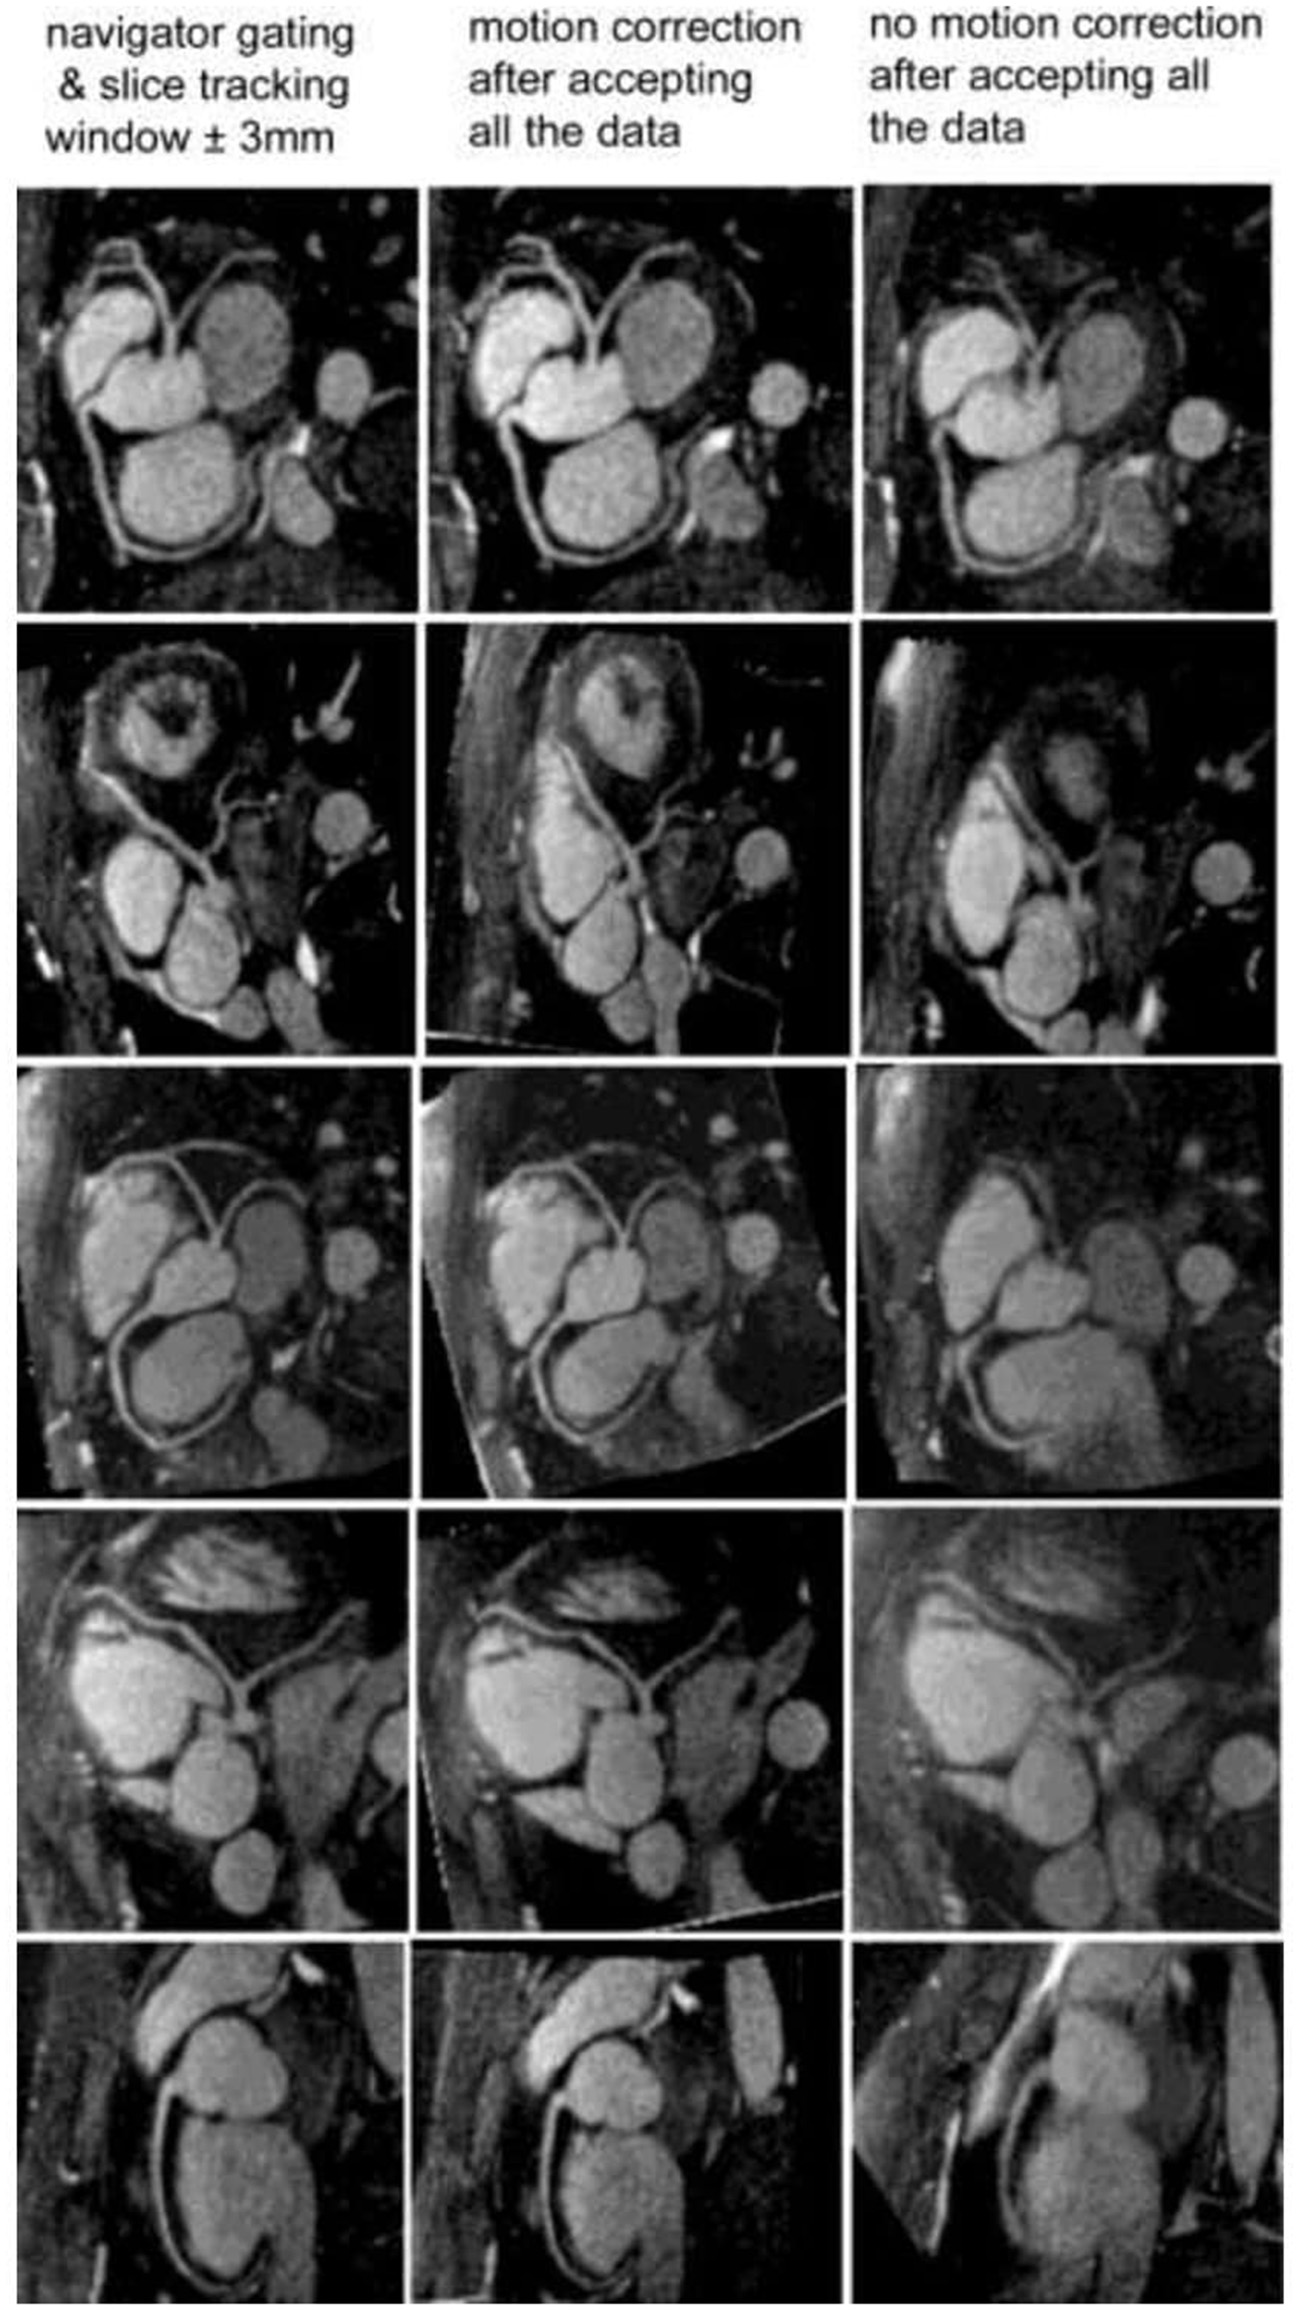

It is possible to combine an undersampled 3D radial trajectory acquisition with 1D navigators (diaphragmatic or self-navigation) to allocate the acquired data into specific phases in the respiratory cycle (respiratory bins). Registration algorithms subsequently assess the motion between each bin and a reference end-expiratory bin. Images from all respiratory bins are then motion corrected to the common respiratory position and averaged to produce a respiratory motion corrected image. This methodology allows for 100% respiratory scan efficiency with a drastically shorter acquisition time in comparison to respiratory gating alone with similar image quality (Figure 3) (22, 40, 41, 53). Respiratory resolved frameworks have been proposed to further reduce the multidirectional non-rigid motion related artefacts (Figure 4) (54), displaying substantial enhancement in vessel length depiction as well as vessel sharpness in comparison to 1D self-navigation frameworks. This approach has been extended to cardiac phases (so called “5D whole-heart”) from free-running frameworks (Figures 5, 6) (21, 55–57). However, lower signal to noise ratio and prolonged reconstruction time (with compressed sensing) are associated with radial sampling. Spiral trajectory k-space CMRA acquisitions have been proposed to improve scan efficiency, the signal to noise ratio and reduce undersampling artefacts by oversampling near the k-space origin (58–60).

Figure 3

Reformatted coronary artery images from five healthy volunteers. With the motion correction technique (middle column), coronary artery visualization is excellent and similar to the navigator gating and slice tracking approach (left column). Without any motion correction (right column), the images are blurry and the coronary artery visualization is poor. The imaging time with the motion correction technique is reduced by a factor of 2.5 to 3 compared with the navigator gating and slice tracking approach. Adapted with permission from Bhat et al. (53).